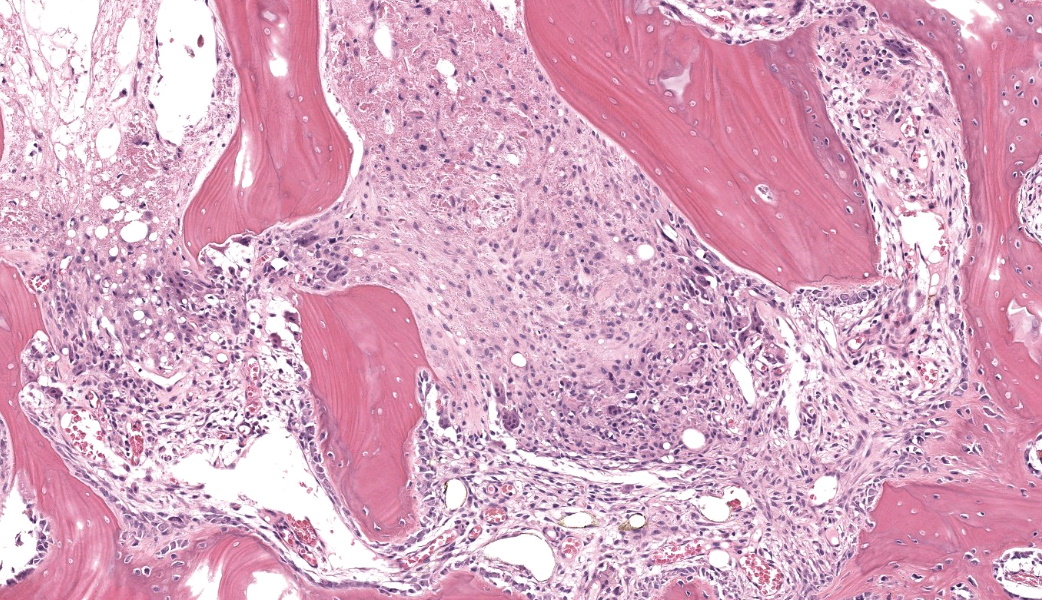

Femoral head: Affecting approximately 30-50% of the epiphysis from the subchondral aspect of the articular cartilage to the physis, there is a focally extensive area of osteonecrosis characterized by bony trabeculae which are irregular and brightly eosinophilic with loss of differential staining. There is loss of both osteocytes within lacunae and osteoblasts lining trabeculae in this region. Along the margins of the necrotic area, multiple bone trabeculae are fragmented and/or have scalloped margins with osteoclasts in Howship’s lacunae (osteolysis). The intertrabecular spaces within and at the periphery of the necrotic area contain variably amounts of amorphous eosinophilic matrix (fibrin), occasional neutrophils and macrophages and/or loosely arranged myxomatous to collagenous matrix with variable numbers of plump spindle cells and capillaries (fibroplasia). Occasionally, there are also finer, irregular trabeculae of paler staining or partially mineralized bone (woven bone). Adjacent viable trabeculae are lined by numerous active osteoblasts (remodeling) and are sometimes laced with wavy basophilic lines (resting / resorption lines). The articular cartilage is fragmented (likely artefact).Contributor's Morphologic Diagnoses:

The contributor of this case gives an excellent overview of this condition.Most of conference discussion was centered on pathogenesis and key histologic features of this condition. This disease can be, as stated by the contributor, either hereditary or secondary to trauma or other ischemic event.1,3,4,5,6 The hereditary form is most often seen in young, small breed dogs, such as terriers, dachshunds, pugs, Chihuahuas, and toy poodles. When looking at this case, there are a few histologic clues that can assist in determining the age of this animal, which can help with reaching the correct diagnosis. These include the presence of discontinuous physeal cartilage and the horizontal orientation of the bony spicules deep to the physis. In dogs, physes typically close around 10 months of age. Physis closure in Legg-Calves-Perthes disease (LCPD) is typically delayed secondary to ischemia of the physeal cartilage and the subchondral bone, which can result in a malformed or improperly angled femoral head.1 Additionally, in young animals, the bony spicules that extend into the metaphysis from the developing stages of the growth plate are oriented vertically (perpendicular) to the growth plate to facilitate the elongation of the bone. In older animals that have closed physes, the bone below the growth plate becomes oriented horizontally (parallel) to the growth plate, effectively “capping” it to facilitate closure of the physes. In this case, the bone has become horizontally oriented below the growth plate, indicating that this animal should have closed physes at this stage, but the presence of and discontinuity of the lingering growth plate indicate that this young animal is likely experiencing delayed physeal closure.

In the early stages (Grade I) of LCPD, the articular cartilage is spared because of its avascular nature.1,3,5 The subchondral bone, however, will become necrotic, and there is frequently a characteristic “tideline” of hypereosinphilia between the unaffected articular cartilage and the affected subchondral bone.3,5 As the condition progresses, however, the joint is subjected to altered conductive forces from abnormal weight-bearing, which places excessive pressure upon the articular surface and ultimately results in articular cartilage loss.1,5 This results in both the flattening of the femoral head from mechanical collapse and in asymmetrical growth between the affected limb and unaffected limb, as this disease is usually unilateral.5 Additionally, secondary to the altered conductive forces through the joint, new woven bone begins proliferating in an attempt to re-stabilize the bone and adjust for the altered force conduction.1 This woven bone is usually seen flanking either side of an area of lamellar bone to create a “sandwich” effect.